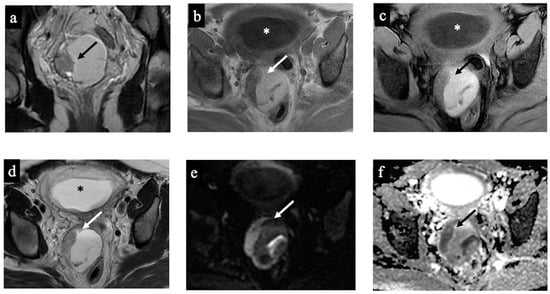

Figure 4. Dermoid cyst. MR images of a 32-year-old woman with an indeterminate adnexal lesion discovered at the first-trimester US. The axial T1-WI (a), T1-WI with fat-saturation (b), T2-WI (c,e), T2-WI with fat-saturation (d), coronal T2-WI (f), axial DWI (g) and ADC-map images (f) show a complex right adnexal lesion with fluid and fatty content. Note the drop of the signal of the fatty component, comparing images (a)/(b) and (c)/(d) (long arrow). The expert radiologist correctly classified the mass as benign/score 2 (true negative). The subtle fatty content, the left external iliac node with a short axis of 10 mm (arrowhead in image (e)), and the presence of tissue with true diffusion restriction within the mass (short arrow in images (fh)), tricked the non-expert radiologist who classified it as malignant/score 5 (false positive).